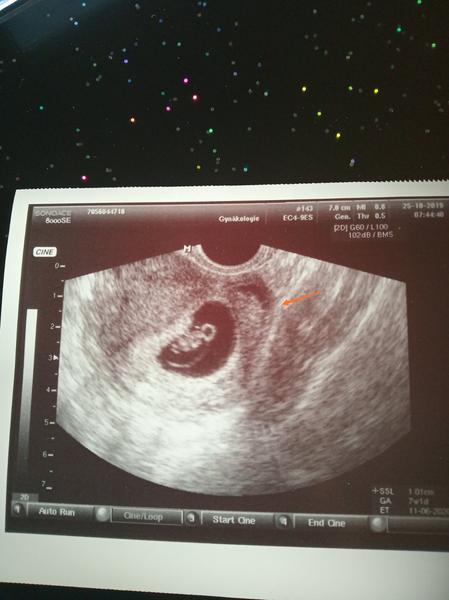

Přítel to omylem pustil ... 2 dny na to plánovaná ms ale kratší. Jsem 4 a půl měsíce po porodu. Cca 4 den po "napuštění" začal prujem s bolestmi celých střev.... Dnes je to 3 den, co ten průjem mám, pořád bolí břicho a ráno jsem málem i zvracela .... ms prakticky pryč (mívám ji 7 dní!) Můžu být těhotná ???

@sudylichozrout je ... Tělísko se chystam, ale řekli mi že můžu až 4tou ms protoze bych si ho vykrvacela měla jsem ze začátku veliké problémy. Chtěli mi ji zastavovat už operativně protože už nebyla možnost jak mi to zastavit. Bylo to šílený. A teď jsem měla už jít ale zase sem nebyla protože jsem nevěděla jestli nejsem v tom .... O mě se otře chlap a je to tam 😥😥😥😁 malá taky vůbec nevím jak vznikla. Pravděpodobně z preejakulátu protože se neudělal do mě ani jednou jedinkrát .... Jen doufám, že tam fakt není.... Na potrat bych nešla a milovali bychom ho stejně ale je to moc brzo po porodu ... Ale když už by bylo, tak co ... Stejně bych s tím nic neudělala 🙂 dostat to prý můžu i přes to že by se případne uhnizdovalo..... Že prý ms z jednoho vaječníků a oplodnění ve druhém nebo co :D nikdy jsem to nezkoumala